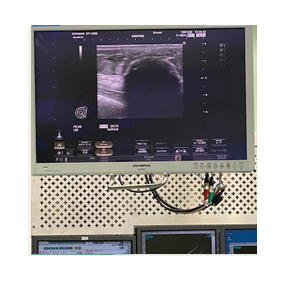

The Icecure Prosense console

The freezing is achieved with liquid nitrogen  which flows through a probe (needle.) The needle is inserted into the tumor under ultrasound guidance. This allows us to position it very precisely, ensuring that the tumor is at the centre of the freezing zone.

This creates a large ball of ice that engulfs the tumor. By alternating freeze and thaw cycles, the cells in the tumor are destroyed. By the end of the procedure there should be no viable cancer cells left. The progress of ice ball development is closely monitored throughout the procedure to ensure safety.